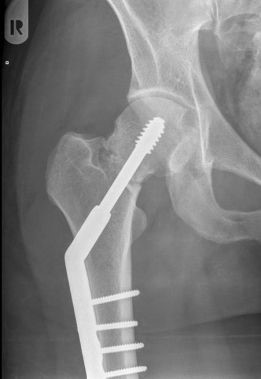

Operatie: in de meerderheid van de gevallen is er een indicatie voor operatie. Het doel van de operatie is de patiënt pijnvrij te krijgen en zo snel mogelijk weer uit bed te krijgen, aangezien patiënten snel zieker worden als ze alleen maar in bed kunnen blijven liggen (ontstaan van oa. longontstekingen en doorligplekken) Het soort operatie is afhankelijk van onder andere de leeftijd van de patiënt, de plaats van de breuk en de stand van de breuk. Als de breuk in de nek van de heup zit (vlak onder de kop), dan zal er gekozen worden voor het vastzetten van de heupkop met bijvoorbeeld 1 of meer stevige schroeven in de heupkop, of voor het vervangen van de heupkop met een heupprothese. Indien de breuk onder de nek en dus meer in het bovenbeen zit, zal er gekozen worden voor of een stevige schroef in een plaat, of voor een stevige schroef met een pen in het bovenbeensbot.